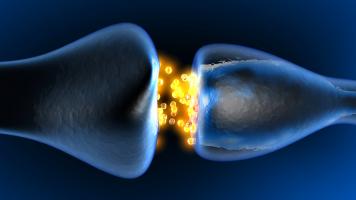

Actualité publiée le 15/12/2019PLASTICITÉ SYNAPTIQUE : Le récepteur clé à 256 configurations en perpétuelle mutation

Actualité publiée le 30/11/2019